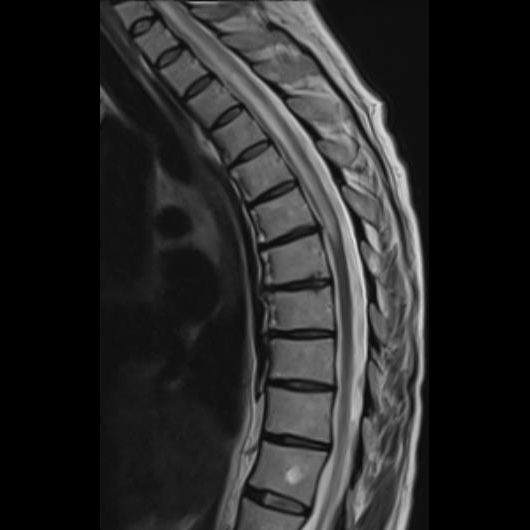

- (A) Torakal MRG’de sagital görüntülerde üst-orta torakal düzeyde T2A hiperintens (oklar), T1A izo-hipointens (ok) uzun segment ekspansil sinyal değişikliği izlenmekte olup sagital postkontrast T1A’da kontrast tutulumu mevcuttur (oklar). Bulgular longitudinal ekstensif transvers miyelit (LETM) ile uyumludur.

- Transvers miyelit sıklıkla santral gri cevheri etkileyen ve üç veya daha fazla vertebral gövde uzunluğunu etkilemektedir (LETM).

- Olgularının %15’i MS’e benzer şekilde kısa transvers miyelit ile karşımıza çıkabilir.

- Transvers kesitlerde, santral kordu tutma eğilimindedir.

- Omurilik atrofisi ve ekspansiyon/ödem MS’e göre daha fazla görülür.

- Kontrast madde enjeksiyonu sonrasında neredeyse tüm akut NMO lezyonları, yamalı, düzensiz veya periferik olarak kontrastlanma gösterir.